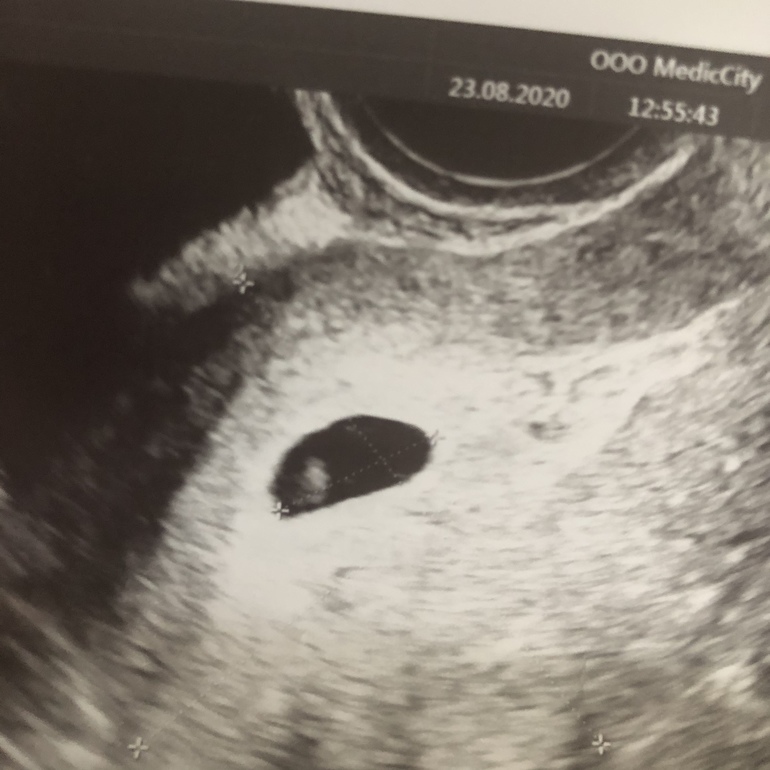

Ура!!! Нашли бусинку!!! ...6 недель. Эмбриона не видно:(

Девочки, сходила сегодня на узи, ПЯ 14мм эмбриона нет, сб соответственно тоже. Сказала переделать через пару-тройку дней, но шансов не много конечно, что появится. Про желточный мешочек сказала, что тоже вроде как нет (в заключении про него вообще не слова)

Но дала вот такие фото... не могу понять что там внутри ПЯ??? Срок по месячным 6 недель. Поздняя овуляция исключена т.к. за 5 дней до мес тест уже был полосатый. Я так понимаю, что в принципе это уже все...:( даже у кого потом находили эмбрион, все равно потом замирал...

Вот то внутри и есть желточный мешочек 😉, шансов ещё много, так что удачи! Сделайте узи через недельку!

Ну я вот тоже думаю, что это желточный мешочек, а она сказала, что его типа нет... поэтому все остальные не слова тоже как бы под сомнением ( хотя врач вроде опытная)

Не торопитесь на узи, не надо через 2-3 дня, сходите через неделю. На фото хорошо видно жм. Эмбриончик может быть слишком мал и находится за жм. Все будет хорошо. 🍀

При анэмбрионии пя будет совершенно пустым, как чёрная дыра. У вас на узи явно там что-то есть. На первом снимке очень напоминает жм, а на втором вообще на эмбрион похоже. Посмотрите сами в интернете картинки с узи на вашем сроке. Думаю, надо просто сходить на узи к другому врачу и все у вас найдут!

Кстати не понятно как она про ЖМ ничего не указала,ведь на нижнем фото видно что делают замеры ПЯ,а на верхнем замеры ЖМ(по линиям и плюсикам)А на нижнем фото я б предположила что вобще эмбрион.

У Вас все в норме по срокам. Размер ПЯ позволяет спокойно подождать несколько дней и сходить поискать ктр. ЖМ виден, это тоже + к тому, что все нормально.

Плодное яйцо и желточный мешок , остальное все будет в 7-8 недель)